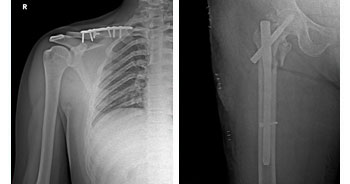

ADVANCED TRAUMA CARE

In any Trauma care center to receive and resuscitate the patient and to save life is our first priority. Saving the limb and other important organs is the next priority.

The hospital follows the principle of Triage, where by the patients are segregated by the surgeons as to have life threatening, limb threatening and other injuries depending on the type of injury, and are given treatment priority as the situation demands. To achieve this, a well-equipped intensive care unit and properly trained surgeons, anesthetists & Paramedical staffs are available, round the clock. Advance techniques in body warming, Sequential compression device, Alpha beds, and remote controlled ICU cots are available keeping the patients comfort in mind. Defibrillators, Ventilators, ABG analyzers, Cardio machine etc., are available to diagnose and prevent major complications.

• Trauma Surgery